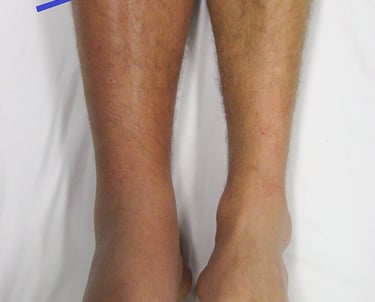

Varicose veins are swollen, curvy superficial veins that lie beneath the skin and are often blueish in colour. Varicose veins are different from thread veins (or spider veins) which are small broken veins that lie in the skin but often both will occur together.

Often the problematic vein is the one running from the groin all the way down to the ankle (great saphenous vein). In patients with varicose veins, some or all of valves along the length of this vein don’t work properly causing this vein and its branches to swell up giving the typical appearance of varicose veins. These branches are often quite superficial and appear as localised bulges beneath the skin called varicosities. Similarly, the vein that runs from behind the knee to the ankle is affected (the lesser saphenous vein) and sometimes other branches are affected.

Typical symptoms of varicose veins include pain and aching, throbbing, a bursting feeling, heavy legs itching and swelling of the ankles. These symptoms are often worse at the end of the day. Varicose veins also cause cosmetic embarrassment. Some people are so embarrassed by the appearance of their veins they avoid wearing shorts or dresses. Research has shown that varicose veins can interfere with quality of life and work and treatment often results in improvement.